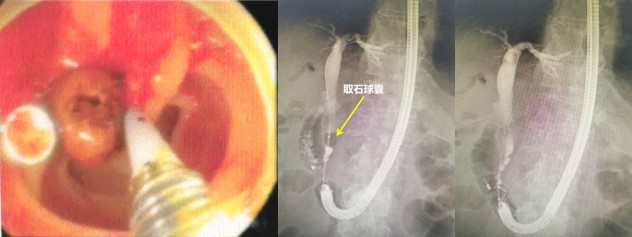

赵刚副主任凭借丰富的经验和精湛的技术,运用胃镜佩戴透明帽顺利找到前期设定的钛夹标记及十二指肠主乳头,然后利用专业器械,在内镜精细操作下,成功进行乳头括约肌切开及球囊扩张术,并最终将胆管内结石顺利取出。整个操作用时不到20分钟。

经过冯建军主任团队悉心周到的术后治疗与管理,刘爷爷在ERCP术后未再出现寒战、发热、腹痛等症状,术后第二天就恢复了饮食,第四天顺利康复出院。